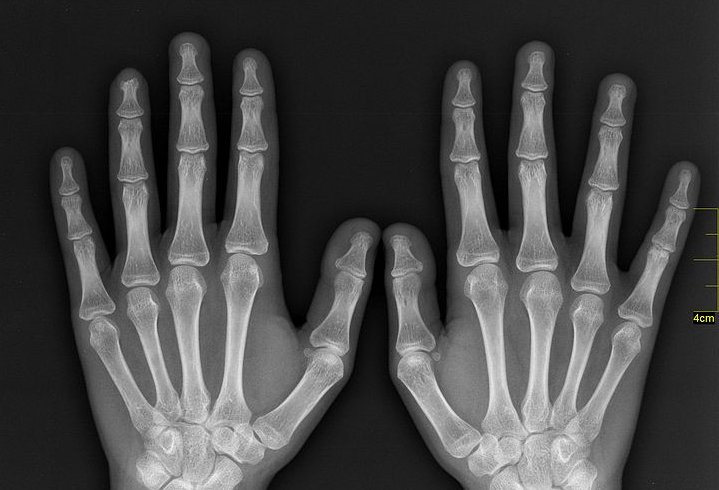

The discovery inspired both horror and hope. Legend has it that upon seeing an X-ray reproduction of her own hand, all bone and metal wedding ring, Rӧntgen’s wife Anna Bertha said, “I have seen my death!” and never returned to the lab. But the medical industry saw in the X-ray a boundless therapeutic potential.

This famous X-ray image shows the hand (and wedding ring) of Anna Bertha Rӧntgen. Wikimedia Commons

Today, basic imaging to create Rӧntgen-like visualizations, which let us peer beneath skin without a scalpel, are offered by every doctor, dentist, and orthodontist in the country. But X-rays have taken on countless new forms in the last 120-odd years since Anna Bertha marveled at her own hand. It didn’t take long for technicians to realize, with a little effort, that the X-ray could show more than just hard substances like bone. For example, by filling a patient with the chemical element barium, doctors were able to visualize the soft tissues of the gastrointestinal tract.